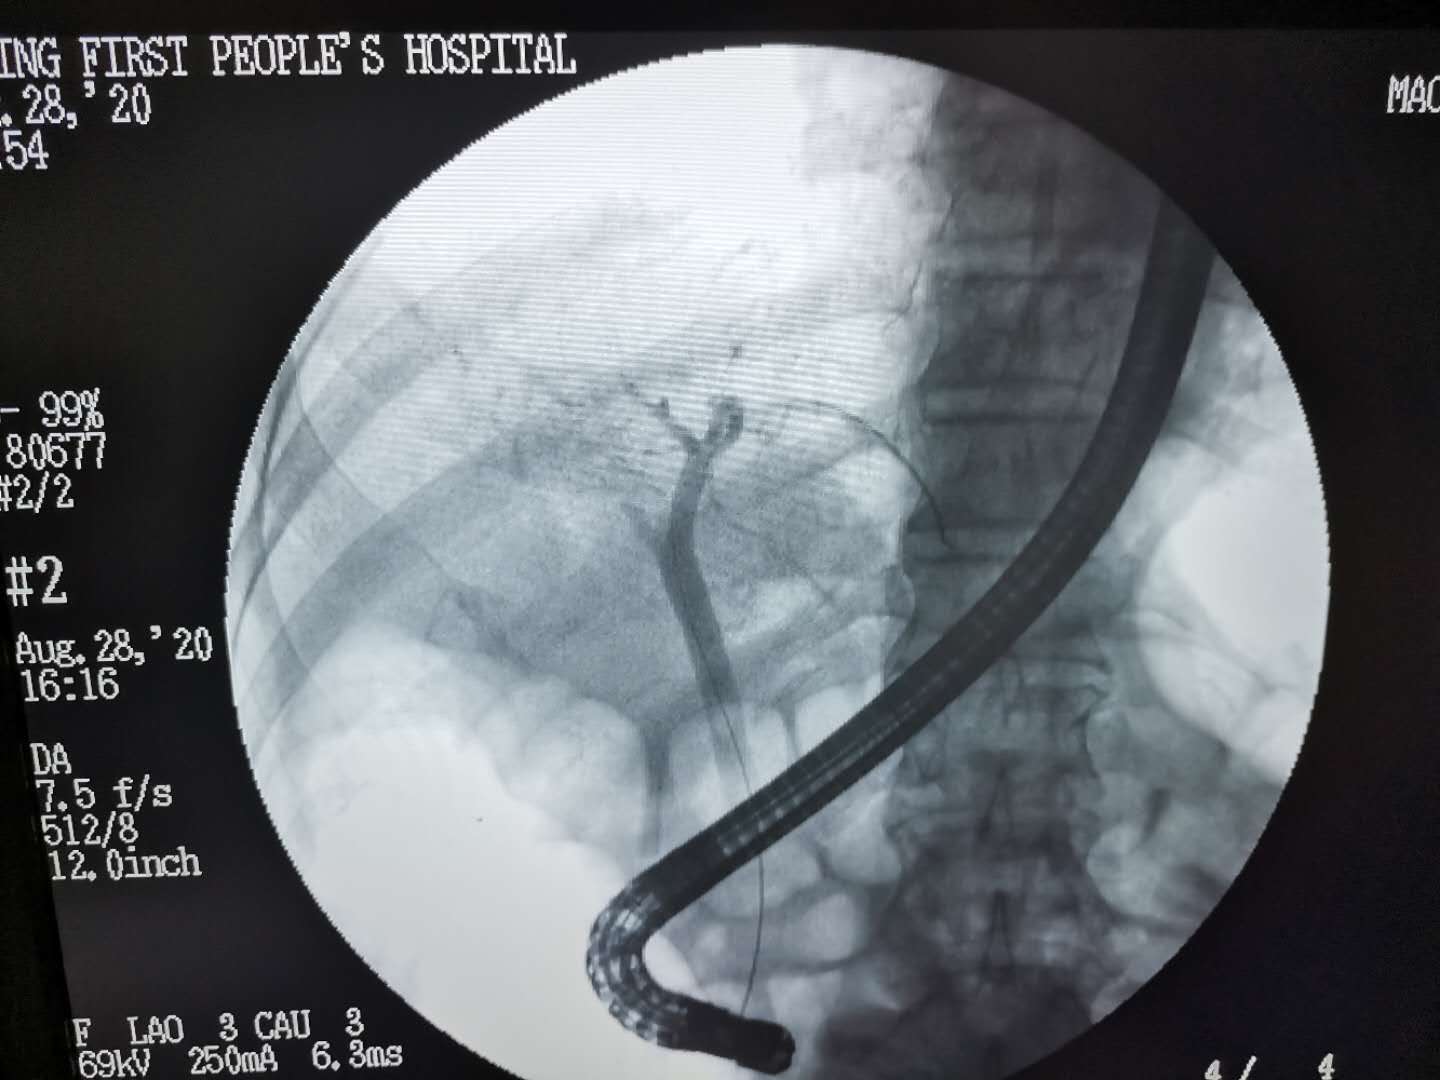

8月28日,由市一院消化内科伍平医生主导,姚成云医生辅助,在X光机下通过一根特殊的镜子,成功为这位86岁高龄患者行ERCP取石术,一枚直径约7毫米的石头,从病人口腔被带出体外,彻底解决了患者的后顾之忧。这根特殊的镜子就是十二指肠镜,它的具体做法跟做胃镜很相似,就是将镜子通过患者口腔插入到胃,经过胃再进入到十二指肠,通过十二指肠乳头插入特殊的器械导丝,把导丝插进胆道后,打入造影剂进行造影。造影之后用X光机来拍片进行透视,观察造影剂在整个胆道的情况来判断结石大小、嵌顿位置,然后切开乳头,球囊扩张后,用网篮取出石头。